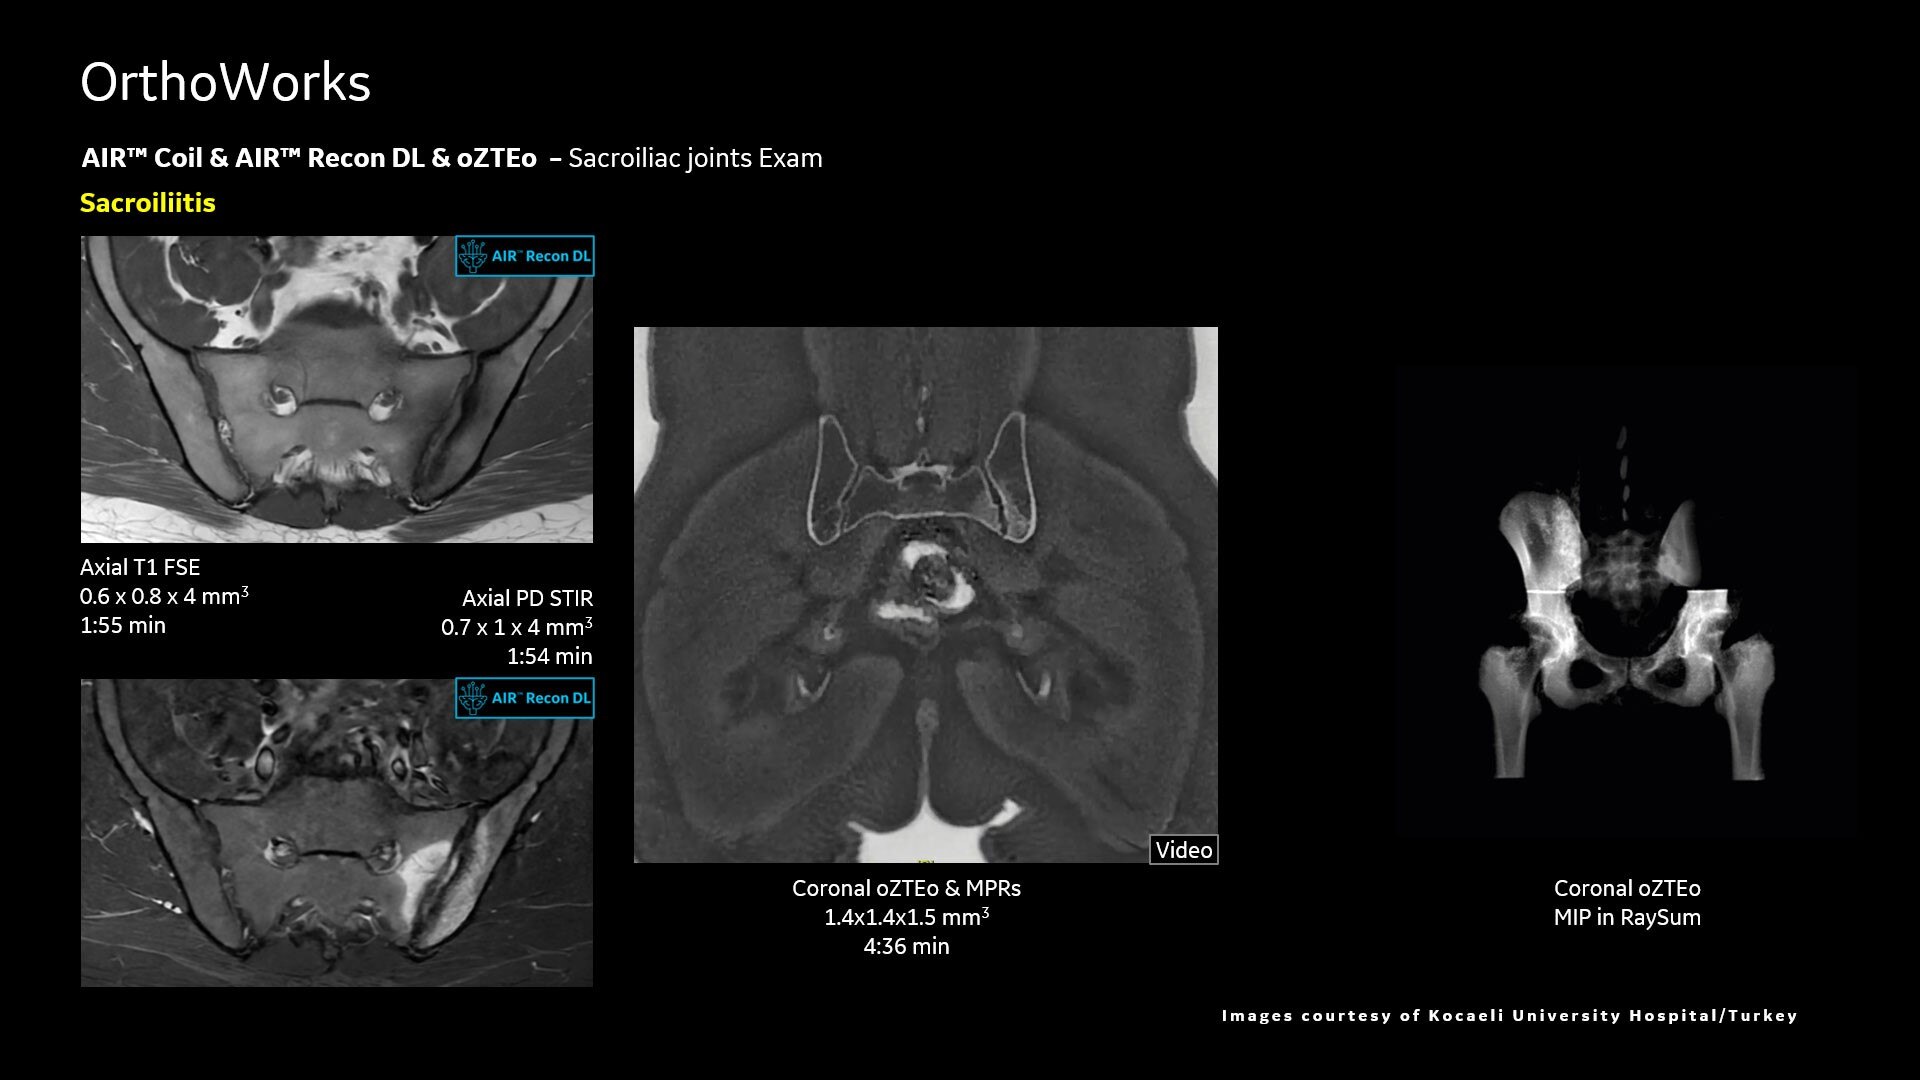

AIR™ Recon DL improves SNR and image sharpness, enabling shorter scan times

Up to 50% faster acquisition time with AIR™ Recon DL